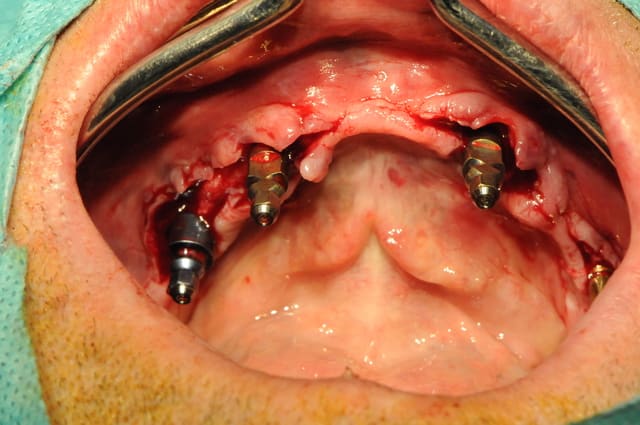

les photos...

pourquoi 4 implants et comment vont fonctionner les cavaliers ?

4 parce que le patient ne peut pas en mettre plus pour l'instant et que cela me permettra de passer plus tard en fixe.

quant à la position des cavaliers, c'est vrai que trois c'est trop, deux latéraux c'est pas super , et, un seul central c'est presque du sur traitement pour en arriver à ça.

mais encore une fois le but est de passer dans les deux ans à du fixe dés que ses finances le lui permettront.